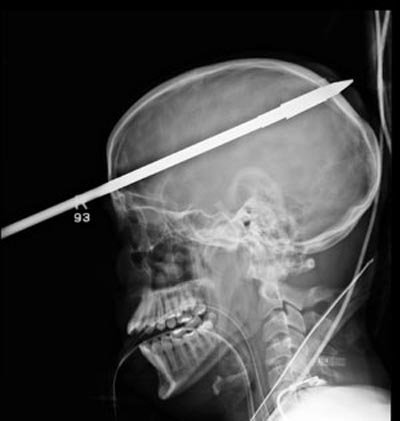

Sau đó, Lopez được trực thăng đưa đến cấp cứu tại Trung tâm Chấn thương Ryder (Bệnh viện Jackson Memorial). Các bác sĩ đã sơ cứu và chụp X-quang vùng đầu. Kết quả cho thấy chiếc xiên đã xuyên thủng hộp sọ và phần não phải của cậu.

Ảnh chụp X-quang cho thấy xiên cá xuyên qua sọ của Lopez. Nguồn: Jackson Memorial Hospital

Các bác sĩ tại Bệnh viện tưởng niệm Jackson tại Miami cho biết mũi tên dài 90cm đã đâm vào trán của Lopez, trên mắt phải 5cm và xuyên qua phía sau đầu.